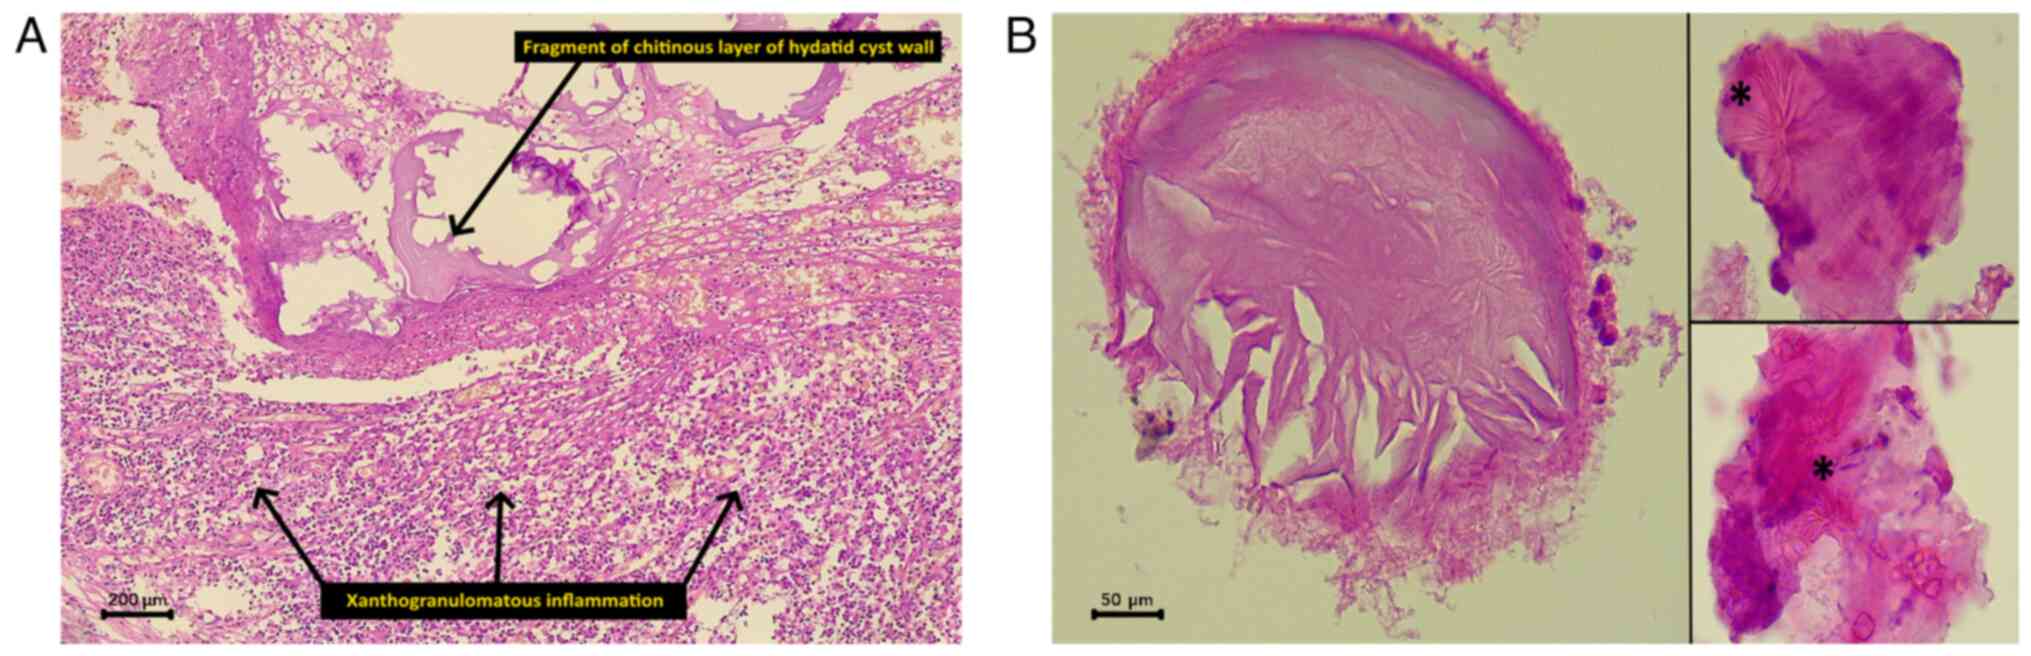

irrigation and layered skin closure. Of note, three biopsy

fragments were sent for a histopathological examination: The

duodenum with the attached head of the pancreas (16.5x8x5.5 cm),

the spleen (11x7.5x3.5 cm) and an irregular gray-brown fragment of

pancreatic tissue (11.5x5.5x2.5 cm). The sections (5-µm-thick) were

paraffin-embedded and fixed with 10% neutral-buffered formalin at

room temperature for 24 h. The sections were then stained with

hematoxylin and eosin (Bio Optica Co.) for 1-2 min at room

temperature and were examined under a light microscope (Leica

Microsystems GmbH). The pancreatic head and the separate pancreatic

fragment had a firm, dull, gray-cut surface with scattered white

areas. A microscopic examination revealed chronic

xanthogranulomatous pancreatitis, consistent with rare acellular

fragments of the hydatid cyst wall and remnants of hooklets from

the brood capsules (Fig. 2). It

was consistent with a reaction to a hydatid cyst. All the

peripancreatic lymph nodes were benign, and the spleen contained a

benign spindle cell tumor, consistent with an inflammatory

pseudotumor.

the intraoperative spillage of the cyst contents. A

histopathological examination confirmed that the hydatid cyst

caused chronic xanthogranulomatous.